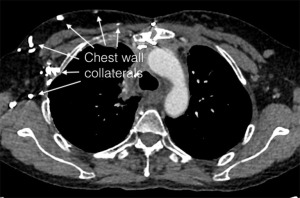

No tumor recurrence was found after a 44-month follow-up and abundant collateral circulations could be seen in postoperative imaging (Figure 3).

The patient already had collateral circulations before surgery and more abundant collateral circulations could be seen after SVC resection alone without venous reconstruction (Figure 6). After a 31-month follow-up, there was no recurrence of tumor (Figure 7).

Collateral circulations may develop after chronic SVC obstruction (11). In case 1, preoperative imaging showed that the patients had an obvious collateral vein on the left side of the aortic arch originating from the left innominate vein but it was hard to know if the collateral circulations could completely compensate for the loss of the SVC-innominate vein route. So, we prepared for venous reconstruction before surgery and used intraoperative IJVP to decide whether to perform the reconstruction. We also found a thick collateral vein (left superior intercostal vein) consistent with the imaging intraoperatively (Figure 2B). IJVP was below 30 cmH2O when clamping the SVC, supposing adequate blood return to the heart. Therefore, SVC and bilateral innominate veins were resected without venous reconstruction, while azygos vein were reserved. In case 2, the tumor invaded inside the SVC and azygos vein was also invaded. When clamping the SVC and azygos vein, IJVP was also below 30 cmH2O and therefore SVC, bilateral innominate veins and azygos vein were resected without venous reconstruction. These patients recovered well postoperatively without severe obstructive complications. Long-term follow-up showed more abundant collateral circulations and no recurrence of tumor.